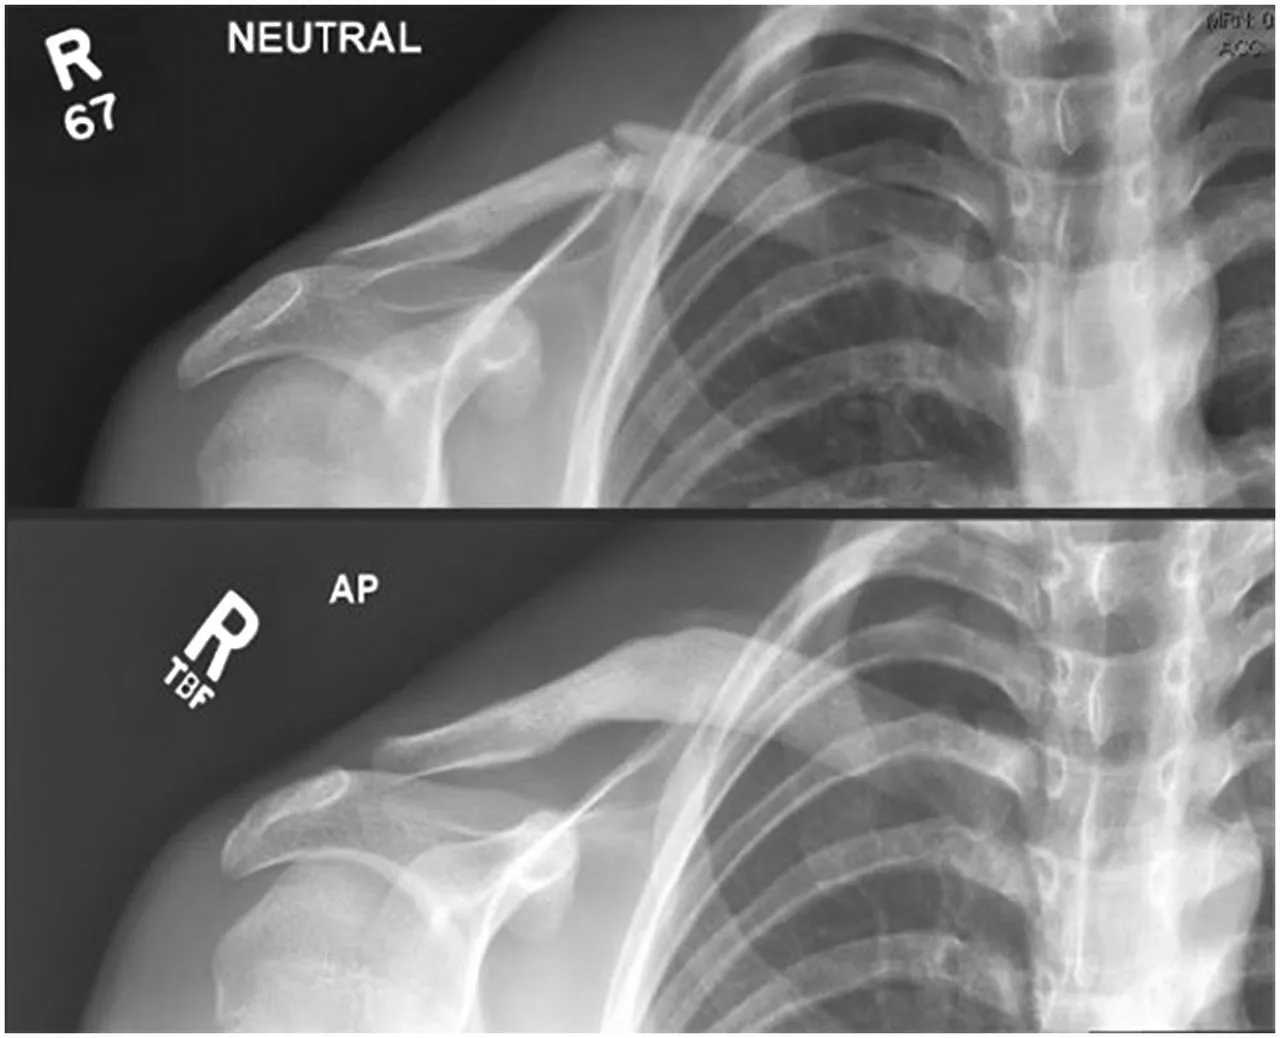

Clavicle (collar bone) fracture

Facts about fractures of the clavicle (Collar bone):

- This is a very common injury in children.

- Most of the time it heals well without any complications using simple painkillers and a sling. However, it can be painful for 4-6 weeks.

- The ‘bump’ over the fracture is normal and is produced by healing bone. It may take up to one year to disappear. If your child is older than 10 years a small bump may remain.

- As these fractures typically heal well without any issue they do not need routine follow up or imaging.